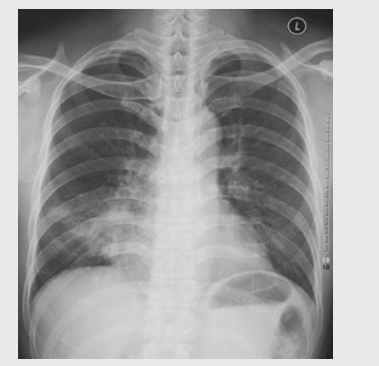

01卷-5.根據下圖請做出正確診斷

A.正常胸片

B.肺門淋巴結腫大

C.肺炎

D.主動脈型心(靴型心)

正確答案:B/D/C/A/A/D/D/D